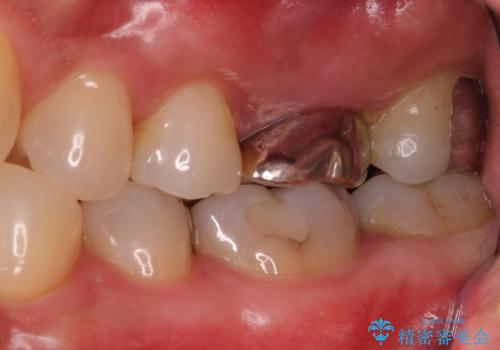

- 左上の奥歯を何とか保存していた患者様です。

今回、残していた歯根から歯茎が大きく腫れ、長期的な予後を期待できないことを考慮し、抜歯してブリッジでの治療を行いました。

- 左上567:仮歯11,000円×3本、ジルコニアクラウン(スタンダード):121,000円×3本 合計396,000円費用は治療当時の料金となります